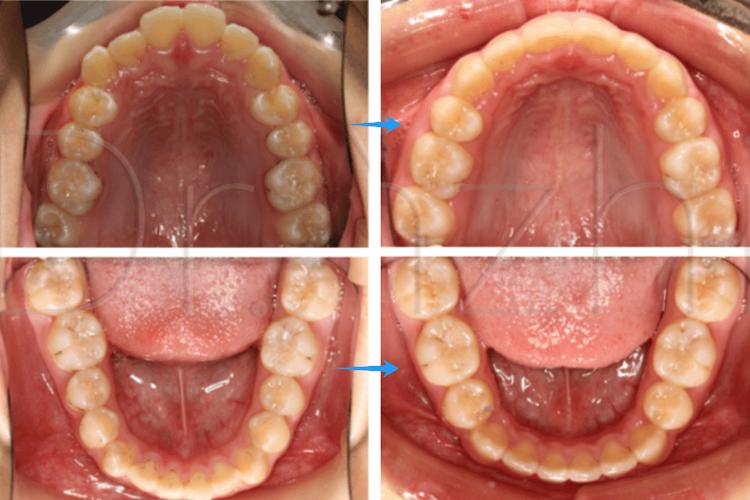

成人牙齿矫正的核心目标是建立稳定的咬合关系、改善面部美学及促进口腔健康,由于成人骨骼发育已完成,牙齿移动速度相对青少年较慢,且常伴有牙周问题、牙齿磨耗等情况,拔牙在成人矫正中不仅是解决空间不足的手段,更是规避矫正后复发、保证长期疗效的关键,对于严重拥挤的牙齿,若强行排齐而不拔牙,可能导致牙齿前突加重、嘴唇外翻,或因牙弓扩展不足导致牙龈萎缩、牙根暴露;对于咬合紊乱的患者,拔牙可调整磨牙关系,避免颞下颌关节负担过重。

对于轻度拥挤或不愿拔牙的患者,可选择替代方案,如邻面去釉(磨除少量牙釉质,每颗牙可获取0.25-0.5mm空间)、磨牙后推(将后牙向远中移动)或扩弓(扩大牙弓宽度),但需严格评估适应症,避免导致牙龈萎缩或咬合紊乱,需注意,替代方案对拥挤度的改善有限,重度拥挤仍需拔牙。